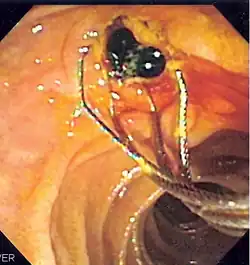

Ретроградная холангиопанкреатография (РХПГ; англ. Endoscopic retrograde cholangiopancreatography, ERCP) — эндоскопический метод исследования жёлчных протоков и протока поджелудочной железы, сочетающий эндоскопию с рентгеноскопическим исследованием. Является одновременно диагностической и лечебной процедурой.

1. Премедикация (седация или общая анестезия) 2. Введение дуоденоскопа через рот, пищевод и желудок в двенадцатиперстную кишку к большому дуоденальному сосочку 3. Катетеризация протоков с введением рентгеноконтрастного вещества 4. Рентгеноскопическая визуализация протоковой системы